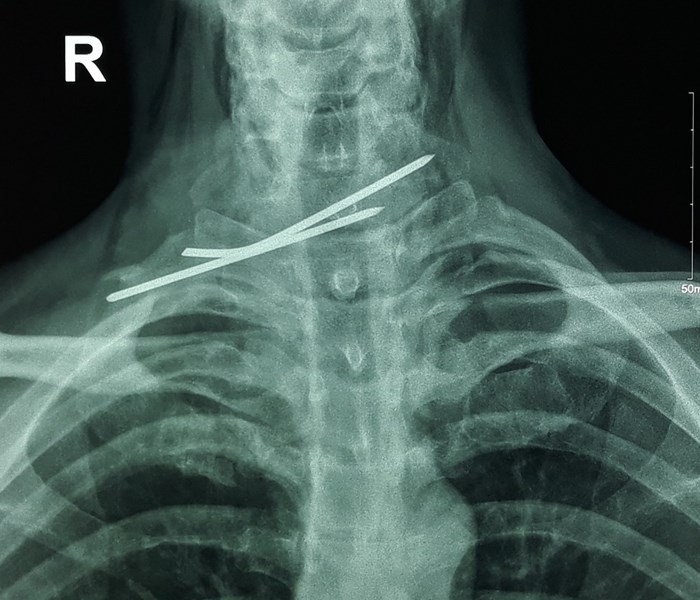

Phim chụp X-quang cho thấy cây kim đâm xuyên thực quản và khí quản

Trước đó, ngày 5.9, anh Nguyễn Văn Ph. (41 tuổi ngụ huyện Trần Đề, Sóc Trăng) nhập viện trong tình trạng nuốt đau, ho khạc ra máu. Qua thăm khám và làm các cận lâm sàng, bệnh nhân được chẩn đoán xác định có dị vật vùng cổ do đinh kirschner kết hợp xương đòn đâm xuyên thực quản và khí quản.